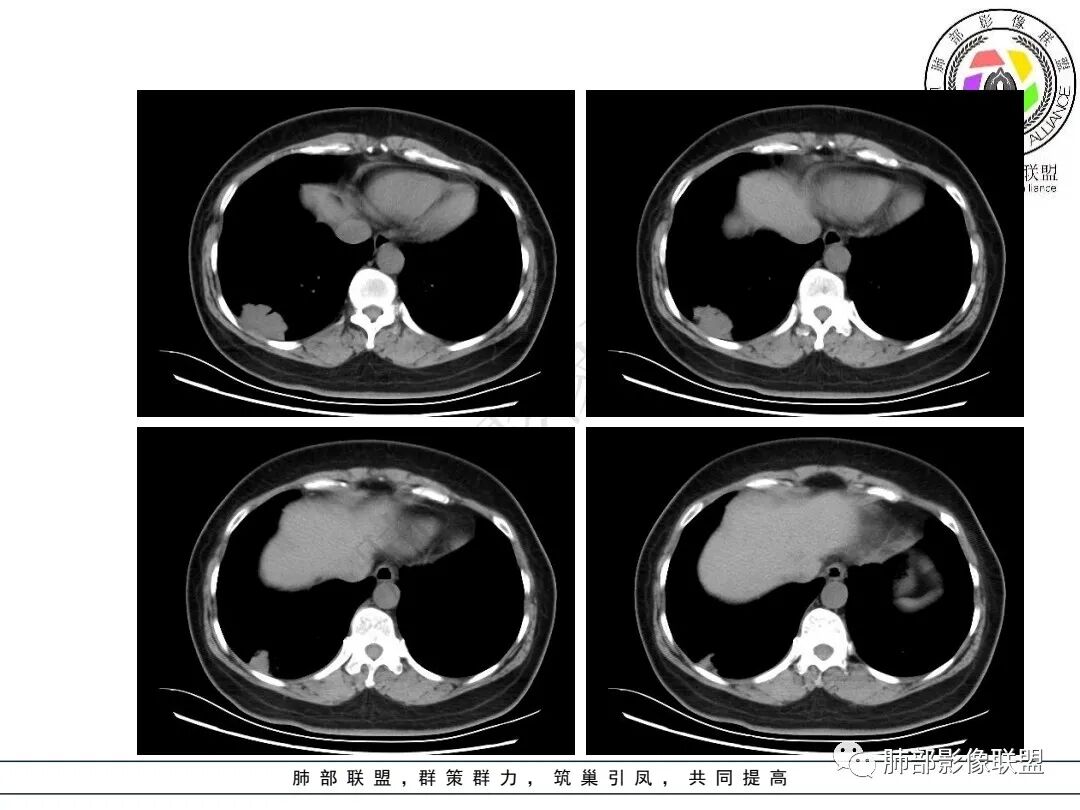

1.患者年龄不详,没有相关临床症状(体检发现)。

2.右肺下叶近胸壁处团片影,边界较清楚,表面欠规则,较均匀实行密度为主,边缘可见边界较清楚的磨玻璃密度区。相邻胸膜增厚,胸膜下隐约见液性密度区,壁层胸膜未见突破蔓延(栽赃)及凹陷。

3.病灶轻度强化,可见血管支气管进入,未显示“脐凹征”或“血管集束”。

4.肺门及纵隔未见增大淋巴结。